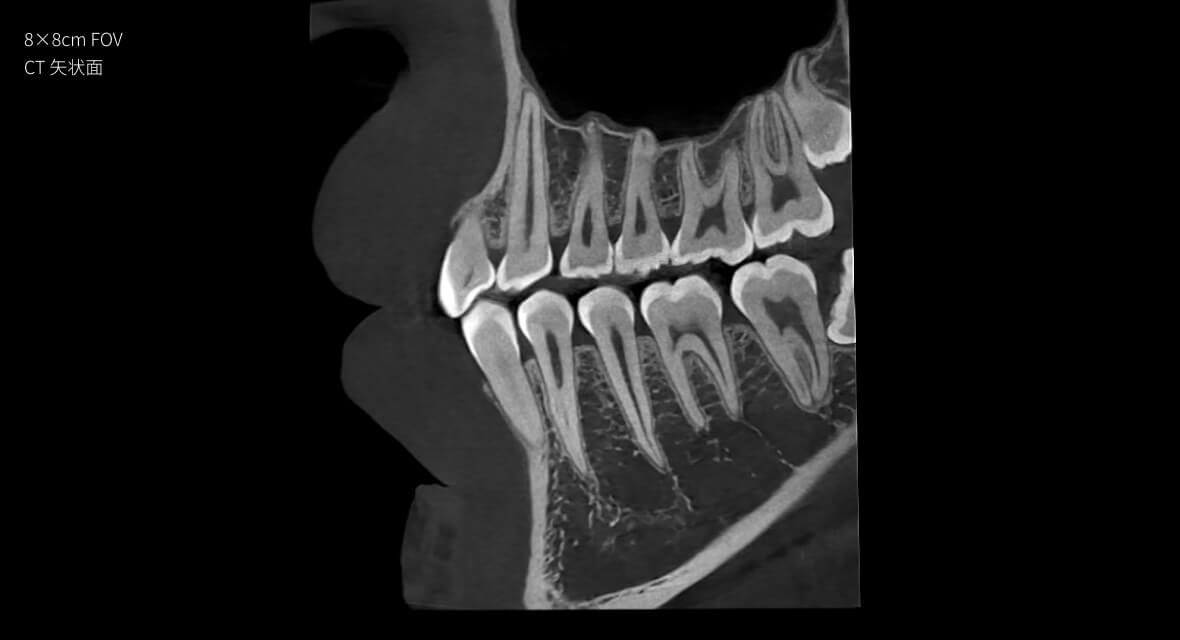

信CT

业界首款螺旋口腔CBCT

• 高精准

28 lp/cm

空间分辨率

28lp/cm

高精准